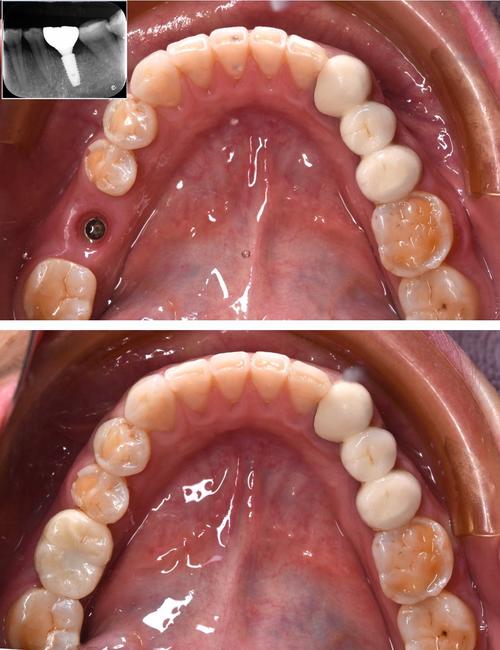

种植牙的原理是通过外科手术将纯钛种植体植入牙槽骨内,作为人工牙根,待其与骨组织结合(骨结合)后,再安装基台和牙冠,实现功能与美观的恢复,全口无牙患者能否种牙,核心取决于牙槽骨的条件——包括骨量(高度、宽度、密度)、骨质量以及是否有影响愈合的全身因素。

对于骨量充足、无严重炎症的患者,可在拔牙后立即植入种植体(即刻种植),甚至结合数字化导板技术,实现“当天种牙、当天戴牙”(即刻负重),避免传统种植需等待3-6个月骨结合的漫长周期,但需严格评估适应证,并非所有患者都能适用。

| 基台与牙冠安装 | 二次手术(若需)暴露种植体,安装基台,取模制作牙冠(全瓷/烤瓷牙冠) | 2-3周 |